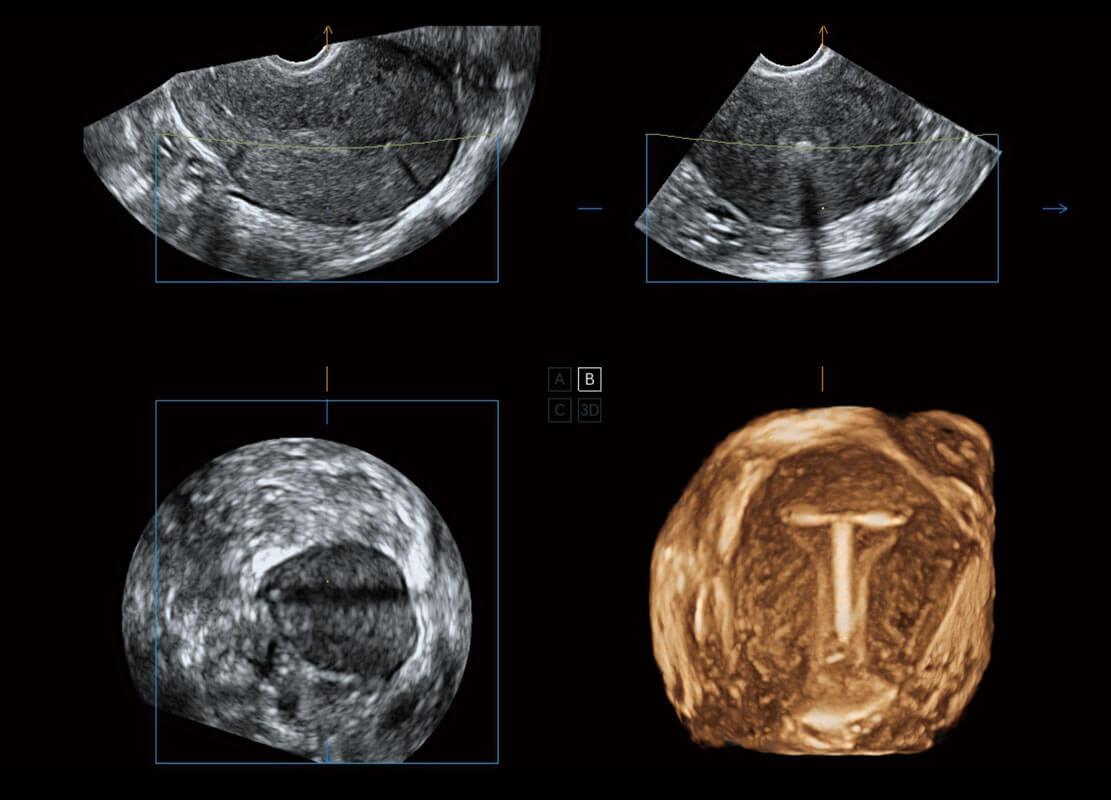

生殖健康

P60优异的图像质量搭载专科探头,在妇科基础疾病的诊断、卵泡生长的监测、输卵管通畅情况的判别等方面为您提供生殖应用方案。

• 腔内三维-宫内节育器